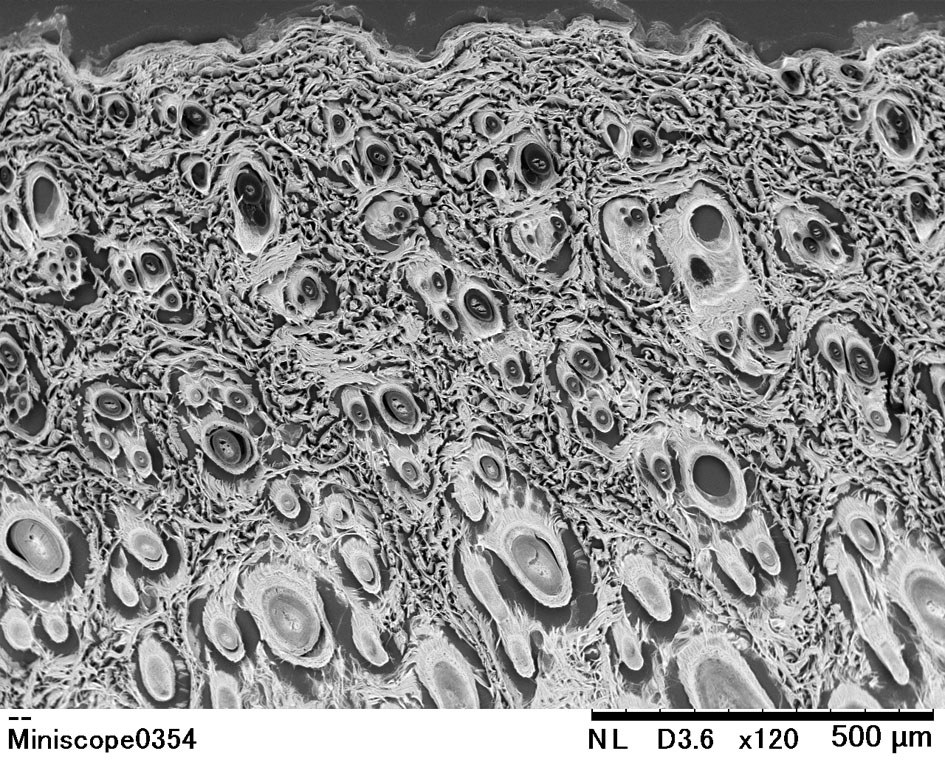

腸 皮膚 上皮細胞 走査型電子顕微鏡 生物学 断面 の画像素材 写真素材ならイメージナビ